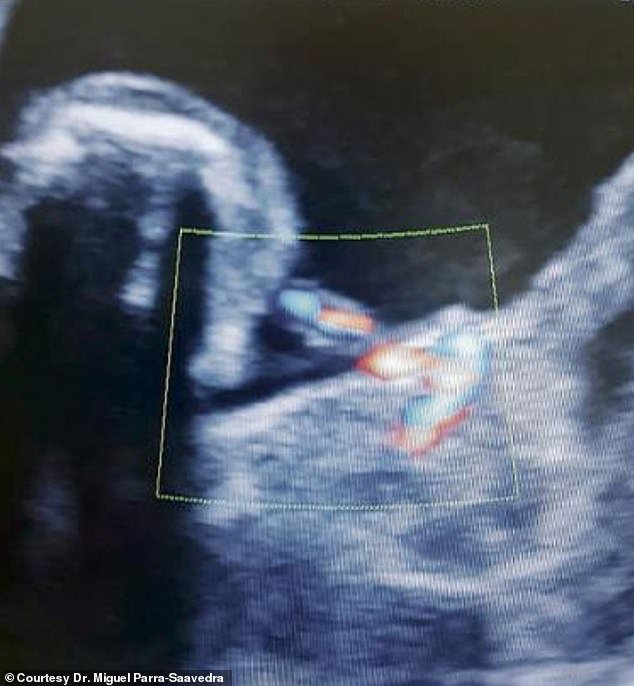

Εγκυος γεννήθηκε ένα κοριτσάκι στην Κολομβία στρέφοντας επάνω του τα φώτα της παγκόσμιας ιατρικής (και μη) κοινότητας.

Η περίπτωση δεν είναι μοναδική, συμβαίνει περίπου 1 στις 500.000 κυήσεις και είναι περίπου η 100η από το 1808. Είναι δηλαδή μια εξαιρετικά σπάνια ιατρική περίπτωση. Η περίπτωση ονομάζεται fetus in fetu. Τι συμβαίνει; Ουσιαστικά πρόκειται για μια δίδυμη κύηση που όμως το ένα παιδί μεγαλώνει στην κοιλιά του άλλου.

Δηλαδή, μέσα στην κοιλιά του κοριτσιού από την Κολομβία μεγάλωνε το αδελφάκι του.

Οταν ο γιατρός της εγκυμονούσας κατάλαβε τι συνέβαινε στον 7ο μήνα, έκανε αναγκαστικά καισαρική στη μητέρα για να μην κινδυνεύσει η μικρούλα, καθώς όσο αναπτυσσόταν το έμβρυο στην κοιλιά του κινδύνευε από πολυοργανική βλάβη.

Αμέσως το νοεγέννητο -το οποίο έχει πάρει το όνομα Ιτζαμάρα- υποβλήθηκε σε μια λεπτή χειρουργική επέμβαση κατά την οποία αφαιρέθηκε από την κοιλιά του το αδελφάκι του. Βρισκόταν μέσα στο δικό του αμνιακό, σάκο, είχε μήκος 45 χιλιοστά και βάρος 14 γραμμάρια, σχηματισμένα άκρα και κεφάλι, αλλά δεν είχε καρδιά και εγκέφαλο.

Για την ιστορία να σημειωθεί ότι ο πρώτος γιατρός της μητέρας, Μόνικα Βέγκα της είπε ότι διέκρινε στον υπέρηχο πως το μωρό της είχε κύστη στο συκώτι. Τότε η νεαρή εγκυμονούσα πήγε σε έναν γυναικολόγο που αναλαμβάνει κυήσεις υψηλού ρίσκου και εκείνος ανακάλυψε ότι το έμβρυο απλά κυοφορούσε ένα άλλο έμβρυο!